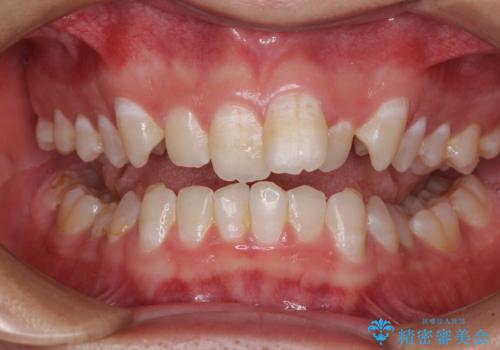

- 強い咬み合わせと前歯のデコボコを気にして来院された患者様です。

下顎前歯が全て隠れてしまうほどの深い咬合で、左右の奥歯は1歯対1歯で咬み合う状態でした。

前方に移動している上顎臼歯を補助装置にて遠心移動させることで1歯対2歯の臼歯咬合を目指し、同時に深い咬合を改善していくこととしました。